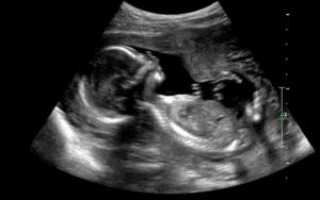

Для точной диагностики проводится абдоминальное или влагалищное ультразвуковое исследование.

Сердце плода узи срок. Узи при беременности.

Ребенок на 18 неделе активно растет и развивается. Будущая мама начинает чувствовать нежные движения ребенка. Беременные с нетерпением ждут этого, так как первое шевеление является одним из самых волшебных событий в течение всей беременности.

Органы ребенка начинают функционировать с восемнадцатой недели беременности. В связи с этим женщина может испытывать некоторые спазмы и заметить белые, выделения из влагалища. Ребенок сейчас примерно 200 грамм и его рост около 1 сантиметров в длину. Его легочная и сосудистая системы стремительно развиваются.

Ребенок может глотать околоплодные воды и производить меконий. Меконий — первое испражнение, которое он сделает. Это хорошая новость, так как это значит, что его пищеварительная система начинает работать. На этой неделе развиваются отпечатки пальцев, создавая уникальный рисунок руки ребенка. Теперь еще больше кровеносных сосудов можно увидеть через его прозрачную кожу.

Боли на 18 неделе беременности вполне нормальное явление. Растяжения коже, и рост живота могут вызвать боль и судороги в нижней части живота. Это пугает многих молодых мам, но это совершенно нормально. Боли на 18 неделе связаны с напряжением матки, и так как матка становится, все больше связки находятся в напряжении.

Боли в 18 недель беременности могут быть острыми и могут ощущаться по обе стороны от живота. Как правило, спазмы быстро утихают. Тем не менее, если на 18 неделе болит живот, то следует обратиться к врачу. Нужно обратить внимание как спазмы приходят и уходят, и насколько они регулярны, и какой между ними интервал.